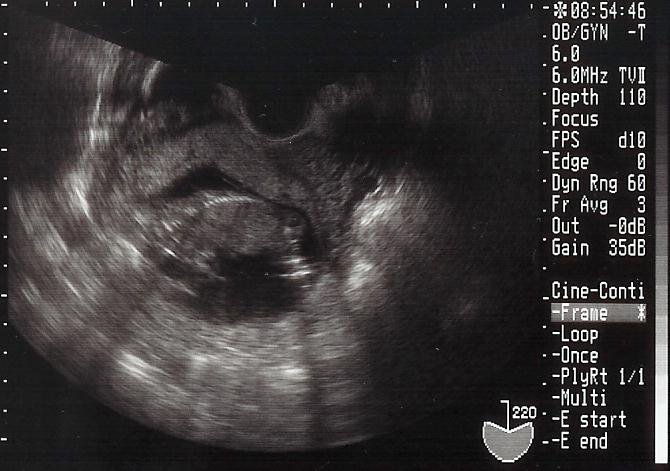

2004年10月15日(金)

13週0日

この日は初期検査の結果を聞くために病院へ行きました。ママは異常なしの健康体!これだけが取り得ですからね。

写真がブレて判りづらいけど背骨が見えるかな